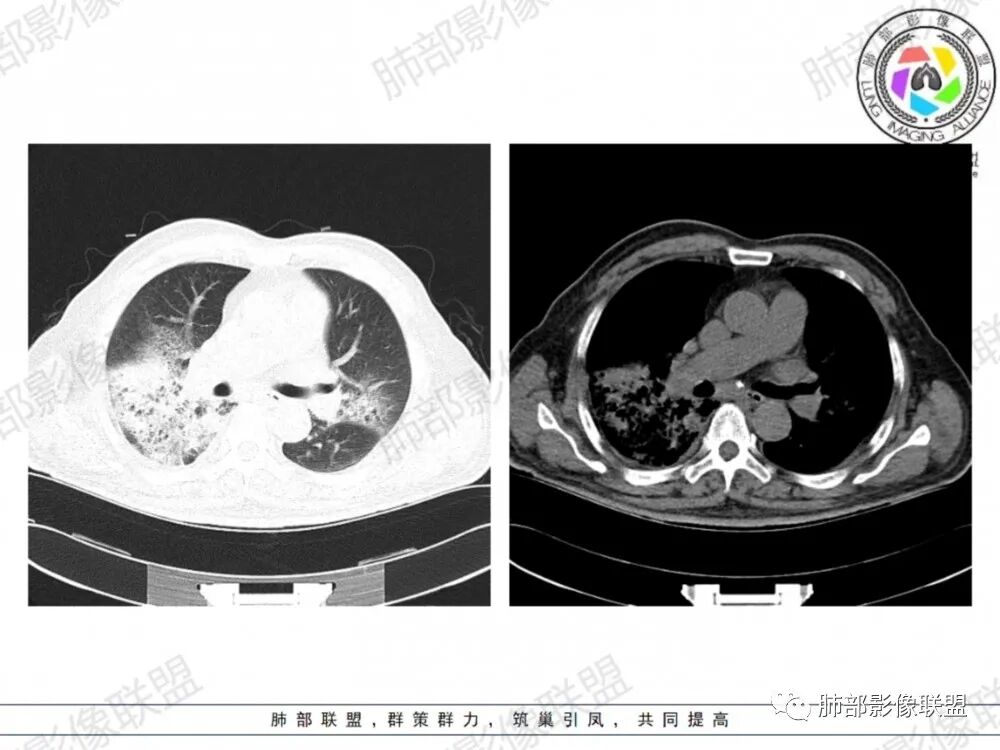

晨读:老年男性患者,咳嗽气喘3天入院,伴有发热,体温38.2℃,有糖尿病,高血压病史,有长期吸烟史,近期旅游史,白细胞,中性粒,CRP,PCT增高,肝功能损害,血气分析:低氧血症,胸部CT:双上肺及右下肺实变密度影伴周围磨玻璃密度影,边界整体清楚,内部支气管走形自然,伴双侧少量胸腔积液,综合考虑感染性病变,重症社区获得性肺炎,重点考虑非典型病原体,军团菌可能,鉴别肺克,结核合并感染

晨读老年患者,咳嗽气喘三天,腹泻,有多脏器的损害。有基础病的病史,糖尿病,高血压。旅游病史。两位靠后分布的大片状的实变影及磨玻璃样阴影,跨叶小叶性的分布,支气管充气征。内部的小叶间隔局部增厚。纵隔淋巴结不大,右侧胸腔积液。首先考虑感染性的病变,靠后重力感,肺克雷伯杆菌肺炎。鉴别诊断军团菌肺炎。

双肺多发斑片及大片状高密度影,周围伴磨玻璃影,界欠清晰,内见多发囊状透亮影呈蜂窝状,病变内支气管走形规则,无肺气肿背景,双侧胸腔积液,老年男性,糖尿病史,消化道症状,炎性指标升高,考虑军团菌感染,克雷白杆菌感染待排。

双肺大片磨玻璃影伴实变,边缘清晰,支气管通畅,磨玻璃影部分呈细网格状,胸膜下清晰,双侧胸腔积液,心影增大,心腔密度减低,贫血,考虑肺克,军团菌

胸部CT示双肺弥漫实变影伴周围磨玻璃影,跨叶段分布,可见小叶间隔增厚,支气管充气征,双侧胸腔积液。无明显坏死空洞及树芽征。

CT:双肺多叶段毛玻璃影、实变影、小叶内间质增粗,肺内病变有重力依赖趋势,双侧少量胸腔积液,无空洞、树丫;

网格影还是比较明显,反晕征的壁在胸膜上,总体感觉病灶比较牢固,被钉紧的感觉,还是军团菌多见一些。

军团菌感染可累及多个脏器,肺是主要的受侵器官。军团菌肺炎为广泛多叶分布的炎症。

1.病变复杂多样∶大片状实变影、斑片状模糊阴性,网格状阴性、小结节影。多叶受侵是本病重要影像学特征性改变。

3.呈小叶肺炎状改变,病变大小以肺小叶为单位的支气管肺炎,呈弥漫性的单或双侧分布。局部可融合呈高密度的团片状影像,本病又一典型的影像学特点。

4.病变常伴有胸水出现,肺部阴性多变的情况下伴有胸水形成应高度怀疑军团菌感染的可能。